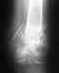

Re: Закрытый трехладыжечный перелом костей правой голени со смещением костных отломков

Хотелось бы увидеть боковую проекцию, но обычно притаких повреждениях гипсовая иммобилизация накладывается на 2,5 месяца, затем ЛФК, физиолечение с восстановлением функции в голеностопном суставе и постепенное увеличение нагрузки. Работоспособность, в зависимости от специальность, восстанавливается от 4 до 6 месяцев. В нашем отделении, при отсутствии противопоказаний, выполняется оперативное вмешательство